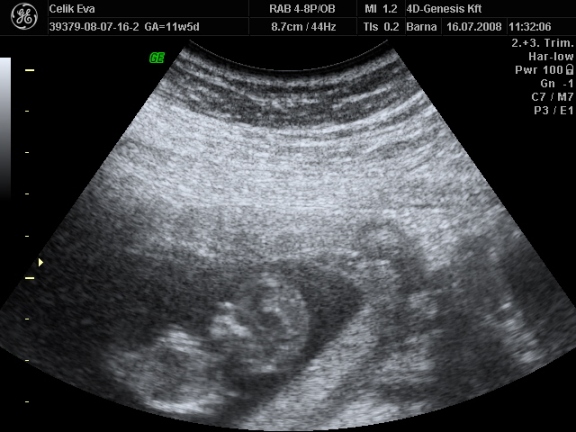

2d-s

ezen olyan aranyos baba arca van :lol: Kép

és a fütyi:

mindegyik deréktól lefelé van, a hasikájának a fele látszik, a lábacskákés közte a fütyi

az első kettő majdnem egyforma

a harmadik is deréktól lefelé de oldal irányból, itt talán jobban látszik a feneke alatt a fütyi mérete :lol:

érdemes a tappancsokat is megnézni :lol: